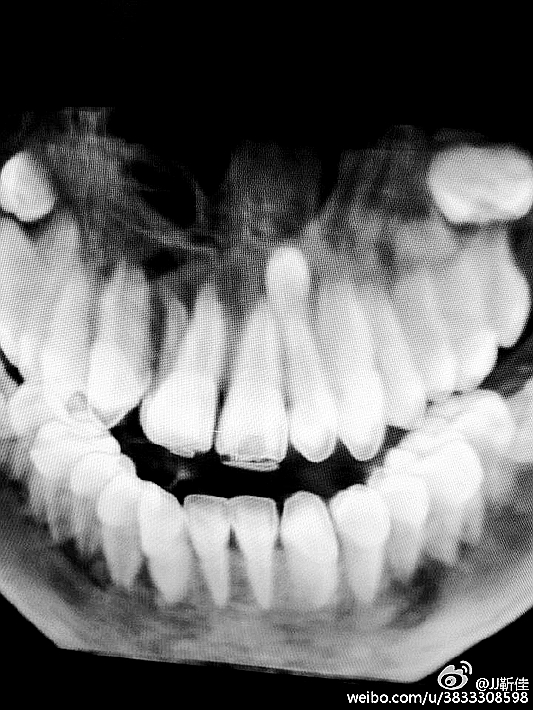

種入植體

今年的額外牙真多啊 男孩14周。

額外牙拔除

好大的額外牙